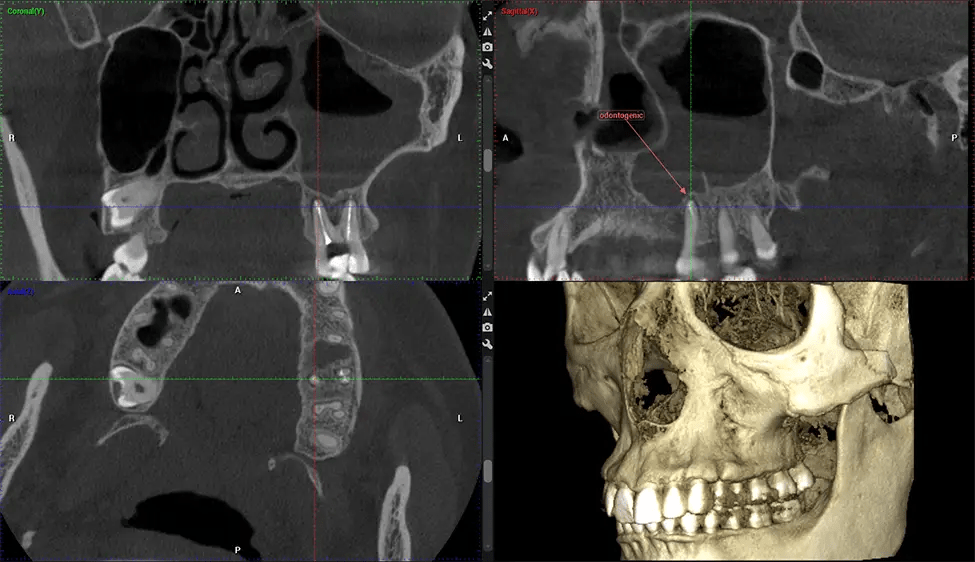

Cone Beam Computed Tomography (CBCT) is an advanced imaging technique used in dentistry and maxillofacial surgery to obtain detailed 3D images of the oral and maxillofacial structures. At Dr G Dental Studio, our CBCT scanners utilize a cone-shaped X-ray beam and a specialized detector to capture images from different angles. A computer then combines these images to create a 3D representation of the patient’s oral anatomy.

This 3D scan, called cone beam computed tomography, gives your dentist a more complete image of your oral anatomy and disease processes than a traditional X-ray. Unlike conventional X-rays, which capture a 2D image of your mouth from various angles, a 3D scan takes multiple digital X-rays for one image. It provides a complete view of your jaw, teeth, nerves, and soft tissues. This enhanced view allows dentists to detect minor issues not visible in traditional 2D scans, such as impacted wisdom teeth or bone fractures in the sinus cavity.

There are many benefits to using CBCT technology, especially compared to the traditional 2D X-ray format. One of the most significant advantages of CBCT scans is that they provide much more information than traditional X-rays. A scan lets your dentist see images from all angles of your jaw and mouth, including your sinuses, nasal cavity, cheekbones, and other surrounding areas. This added information helps your dentist craft a comprehensive treatment plan that addresses all aspects of your oral health.

Another significant benefit is that 3D imaging provides more precise images of your bone structure. These images are more detailed, providing you with a more accurate diagnosis. An accurate diagnosis means better treatment for you.

After the scanning process, the captured X-ray images are processed by the CBCT software, which applies algorithms to reconstruct a detailed 3D image of the scanned area. The software compiles these individual X-ray images and creates a digital 3D representation of the patient’s anatomy. The reconstructed 3D CBCT image can be viewed and analyzed by the dentist or radiologist. This image can be manipulated, rotated, and zoomed in or out to examine specific structures and evaluate the patient’s condition.